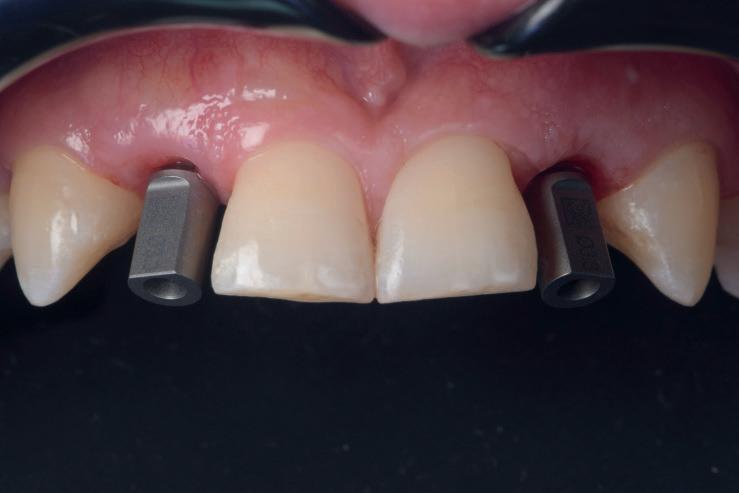

CASE STUDY

Guided implant approach for reproducible results, page 28